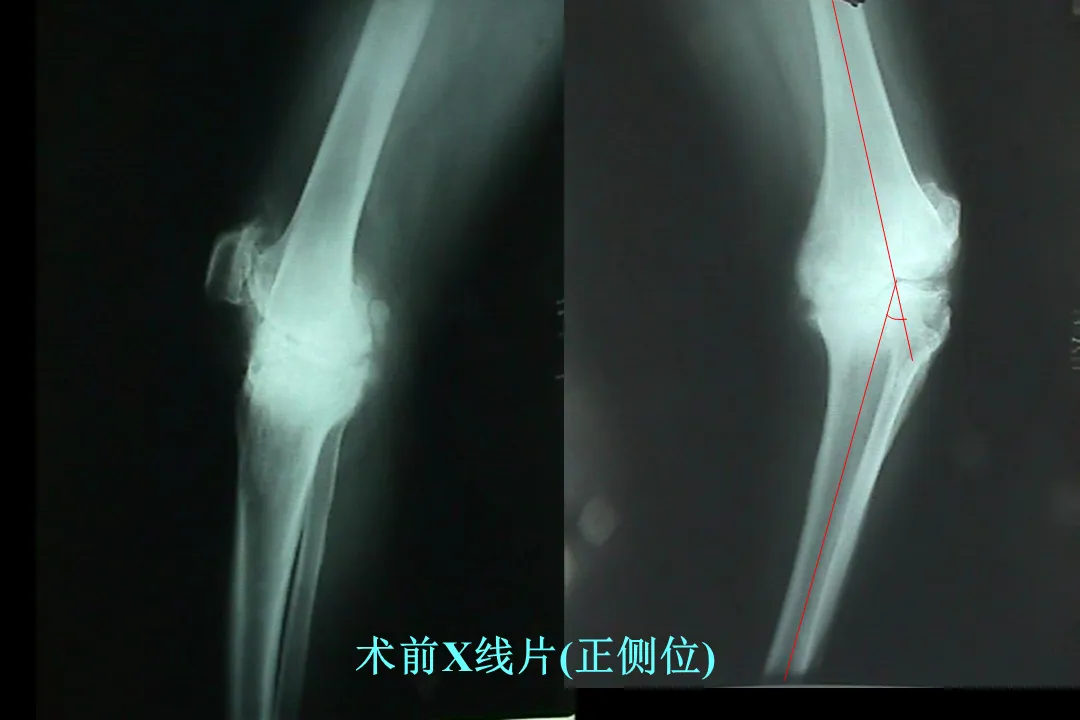

>【骨科PPT】全膝关节置换术软组织平衡

【骨科PPT】全膝关节置换术软组织平衡